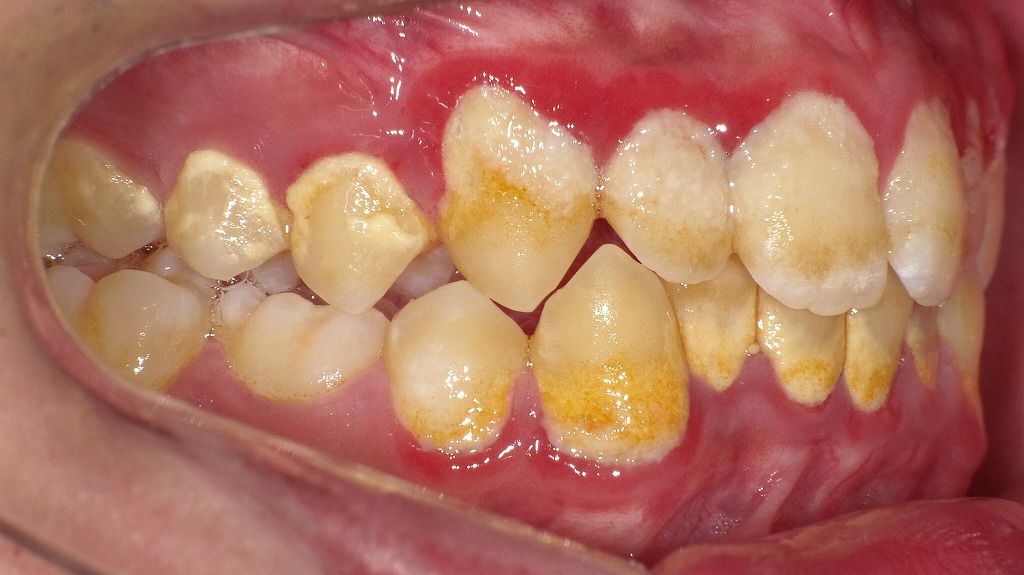

🪨 歯石形成の進行を示す症例

歯石は黄色→茶色→黒褐色へと硬化・沈着が進みます。

この画像では、表面が比較的まだ粗く、形成初期~中等度の段階です。

今後さらに放置すると、歯ぐきの下にも歯石が沈着し、歯周ポケットの拡大・歯周炎進行につながります。

🔴 歯肉炎(しにくえん)

歯ぐきが赤く腫れ、光沢を帯びている部分が見られます。

また、歯と歯の間の歯肉が丸みを帯び、引き締まりがなくなっていることから、歯肉炎の状態が疑われます。

歯石やプラークの刺激によって炎症が起き、ブラッシング時に出血しやすくなる段階です。